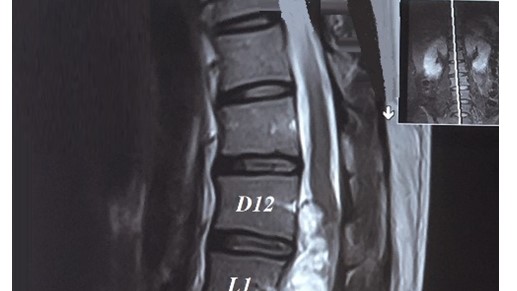

U Schwannoma chóp tủy khổng lồ gây yếu liệt hai chi dưới: Báo cáo trường hợp lâm sàng

ThS. Đinh Thị Phương Hoài, ThS. BSCKII Nguyễn Thanh Minh, ThS. Nguyễn Vĩnh Lạc